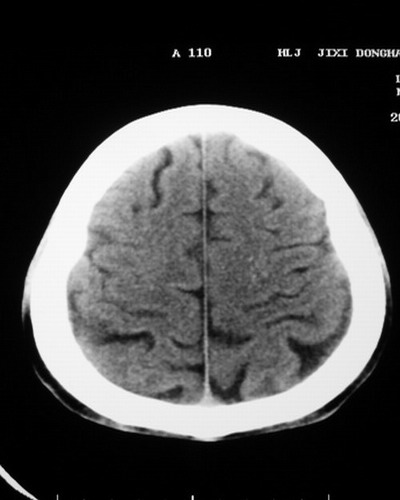

以下是引用随光逐影在2008-1-14 17:26:00的发言:[br]考虑为:甲状旁腺功能低下。需与fahr`s病相鉴别。建议:实验室检查。